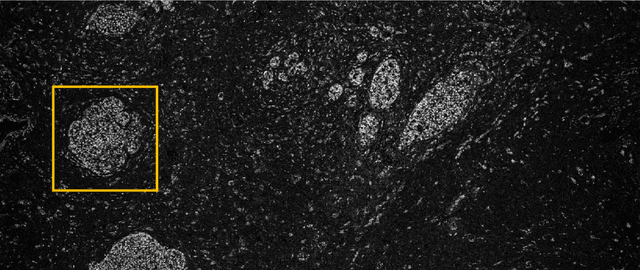

Abstract:Modern histopathology relies on the microscopic examination of thin tissue sections stained with histochemical techniques, typically using brightfield or fluorescence microscopy. However, the staining of samples can permanently alter their chemistry and structure, meaning an individual tissue section must be prepared for each desired staining contrast. This not only consumes valuable tissue samples but also introduces delays in essential diagnostic timelines. In this work, virtual histochemical staining is developed using label-free photon absorption remote sensing (PARS) microscopy. We present a method that generates virtually stained histology images that are indistinguishable from the gold standard hematoxylin and eosin (H&E) staining. First, PARS label-free ultraviolet absorption images are captured directly within unstained tissue specimens. The radiative and non-radiative absorption images are then preprocessed, and virtually stained through the presented pathway. The preprocessing pipeline features a self-supervised Noise2Void denoising convolutional neural network (CNN) as well as a novel algorithm for pixel-level mechanical scanning error correction. These developments significantly enhance the recovery of sub-micron tissue structures, such as nucleoli location and chromatin distribution. Finally, we used a cycle-consistent generative adversarial network CycleGAN architecture to virtually stain the preprocessed PARS data. Virtual staining is applied to thin unstained sections of malignant human skin and breast tissue samples. Clinically relevant details are revealed, with comparable contrast and quality to gold standard H&E-stained images. This work represents a crucial step to deploying label-free microscopy as an alternative to standard histopathology techniques.

Abstract:The field of histology relies heavily on antiquated tissue processing and staining techniques that limit the efficiency of pathologic diagnoses of cancer and other diseases. Current staining and advanced labeling methods are often destructive and mutually incompatible, requiring new tissue sections for each stain. This prolongs the diagnostic process and depletes valuable biopsy samples. In this study, we present an alternative label-free histology platform using the first transmission-mode Photon Absorption Remote Sensing microscope. Optimized for automated whole slide scanning of unstained tissue samples, the system provides slide images at magnifications up to 40x that are fully compatible with existing digital pathology tools. The scans capture high quality and high-resolution images with subcellular diagnostic detail. After imaging, samples remain suitable for histochemical, immunohistochemical, and other staining techniques. Scattering and absorption (radiative and non-radiative) contrasts are shown in whole slide images of malignant human breast and skin tissues samples. Clinically relevant features are highlighted, and close correspondence and analogous contrast is demonstrated with one-to-one gold standard H&E stained images. Our previously reported pix2pix virtual staining model is applied to an entire whole slide image, showcasing the potential of this approach in whole slide label-free H&E emulation. This work is a critical advance for integrating label-free optical methods into standard histopathology workflows, both enhancing diagnostic efficiency, and broadening the number of stains that can be applied while preserving valuable tissue samples.

Abstract:Histopathological visualizations are a pillar of modern medicine and biological research. Surgical oncology relies exclusively on post-operative histology to determine definitive surgical success and guide adjuvant treatments. The current histology workflow is based on bright-field microscopic assessment of histochemical stained tissues and has some major limitations. For example, the preparation of stained specimens for brightfield assessment requires lengthy sample processing, delaying interventions for days or even weeks. Hence, there is a pressing need for improved histopathology methods. In this paper, we present a deep-learning-based approach for virtual label-free histochemical staining of total-absorption photoacoustic remote sensing (TA-PARS) images of unstained tissue. TA-PARS provides an array of directly measured label-free contrasts such as scattering and total absorption (radiative and non-radiative), ideal for developing H&E colorizations without the need to infer arbitrary tissue structures. We use a Pix2Pix generative adversarial network (GAN) to develop visualizations analogous to H&E staining from label-free TA-PARS images. Thin sections of human skin tissue were first virtually stained with the TA-PARS, then were chemically stained with H&E producing a one-to-one comparison between the virtual and chemical staining. The one-to-one matched virtually- and chemically- stained images exhibit high concordance validating the digital colorization of the TA-PARS images against the gold standard H&E. TA-PARS images were reviewed by four dermatologic pathologists who confirmed they are of diagnostic quality, and that resolution, contrast, and color permitted interpretation as if they were H&E. The presented approach paves the way for the development of TA-PARS slide-free histology, which promises to dramatically reduce the time from specimen resection to histological imaging.

Abstract:Significance: Histopathological analysis of tissues is an essential tool for grading, staging, diagnosing and resecting cancers and other malignancies. Current histopathological techniques require substantial sample processing prior to staining with hematoxylin and eosin (H&E) dyes, to highlight nuclear and cellular morphology. Sample preparation and staining is resource-intensive and introduces potential for variability during sample preparation. Aim: We present a novel method for direct label-free histopathological assessment of formalin fixed paraffin embedded tissue blocks and thin tissue sections using a dual contrast photoacoustic remote sensing (PARS) microscopy system. Approach: To emulate the nuclear and cellular contrast of H&E staining, we leverage unique properties of the PARS system. Here the ultraviolet excitation of the PAARS microscope takes advantage of DNA's unique optical absorption to provide nuclear contrast analogous to hematoxylin staining of cell nucelli. Concurrently, the optical scattering contrast of the PARS detection system is leveraged to provide bulk tissue contrast analogous to eosin staining of cell membranes. Results: We demonstrate the efficacy of this technique by imaging human breast tissue and human skin tissues in formalin fixed paraffin embedded tissue blocks and frozen sections respectively. Salient nuclear and extra-nuclear features such as cancerous cells, glands and ducts, adipocytes, and stromal structures such as collagen. Conclusions. The presented dual contrast PARS microscope enables label-free visualizations of tissue with contrast and quality analogous to the current gold standard for histopathological analysis. Thus, the proposed system is well positioned to augment existing histopathological workflows, providing histological imaging directly on unstained tissue blocks and sections.